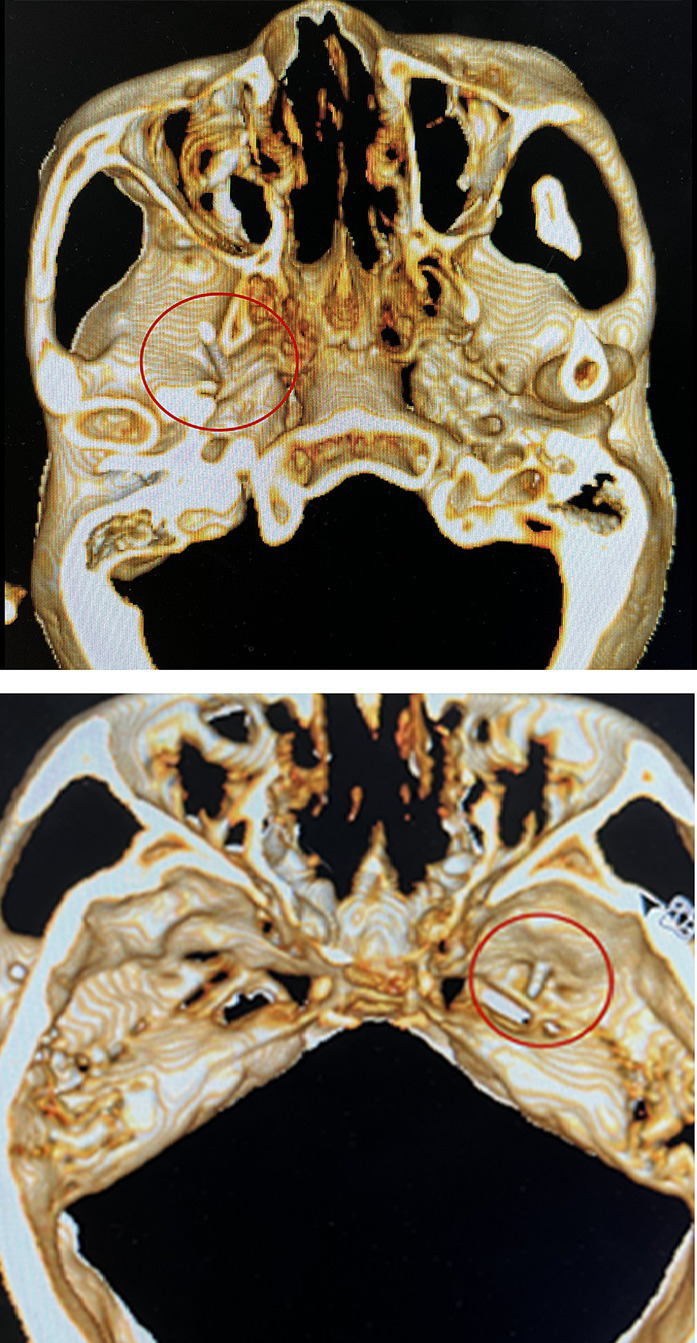

PRT

The patient was placed in the supine position at the back of the head. Blood pressure, heart rate, and oxygen saturation were routinely measured. Before surgery, 0.03 mg/kg midazolam was injected intravenously for sedation. A 10 cm, 22G radiofrequency trocar was used to enter the foramen ovale under CT guidance, and the radiofrequency machine was connected. Sensory stimulation at 50 Hz and motor stimulation at 2 Hz were applied. An abnormal sensation or muscle contraction in the non-diseased area required adjustment of the tip position until the stimulated area covered the painful area, as shown in Figure 3. In addition, local anesthesia of 0.2 mL, 2% lidocaine injection was given. When the pain area became numb, the patient was given three 90-s radiofrequency thermocoagulation at 80°C.

Figure 3

Radiofrequency trocar was used to enter the foramen ovale under the guidance of CT, and the radiofrequency machine was connected. Sensory stimulation at 50HZ and motor stimulation at 2HZ were given. After confirming the location, the patient was given three 90-s radiofrequency thermocoagulation at 80°C.

Notably, for the five patients (20%) in the PRT group who had multiple-branch pain, including the first branch of the trigeminal nerve (V1) pain, we performed radiofrequency therapy of the supraorbital notch (foramen) after the puncture of the foramen ovale. We observed that, even if the location of the foramen ovale puncture was accurate, it was difficult to induce an abnormal sensation in the V1 nerve region, which may be related to the anatomy of the V1 nerve. Nevertheless, supplementary radiofrequency therapy of the supraorbital nerve is required to ensure a therapeutic effect.